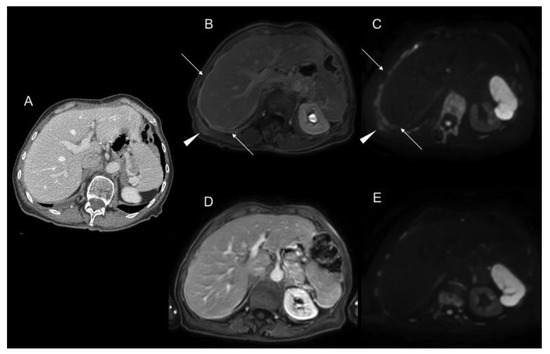

2.1. Computed Tomography (CT)

2.2. Magnetic Resonance Imaging (MRI)

2.4. Imaging Combination